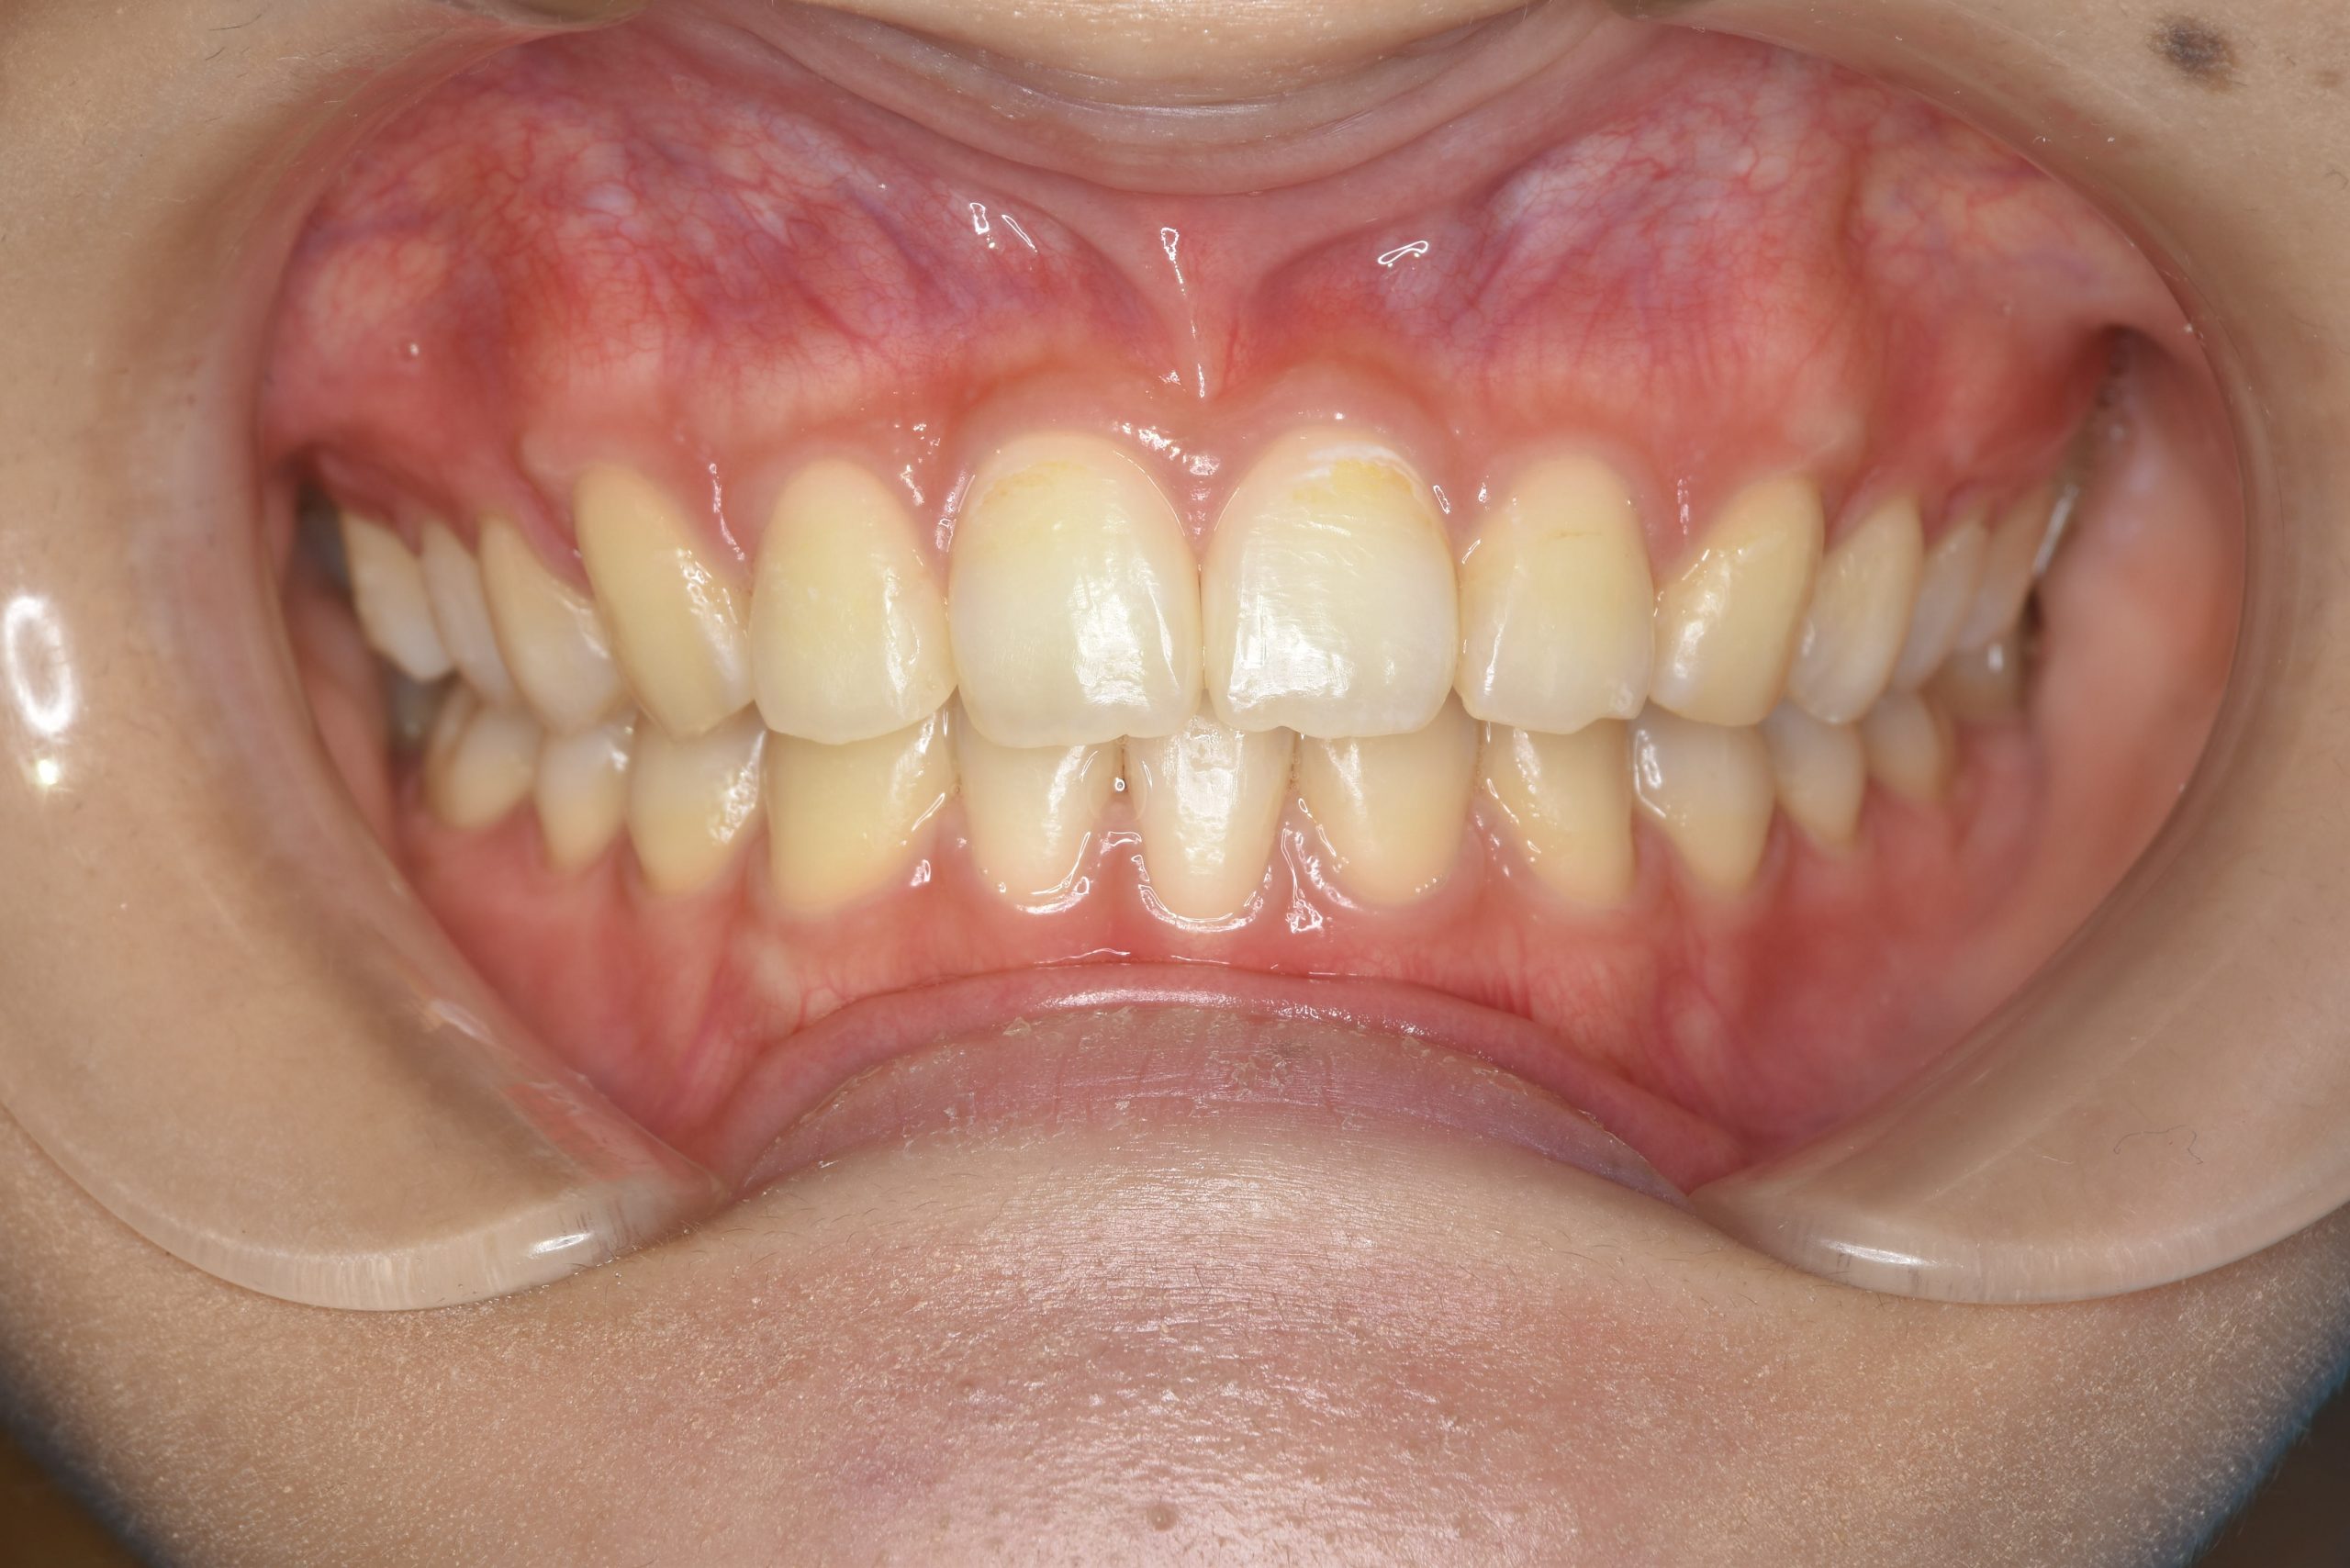

アフター

ワイヤー矯正治療|症例_009

施術内容 MSEと下顎リンガルアーチを用いて上下顎骨を拡大した。

その後マルチブラケット装置とミニインプラントを用いて非抜歯で歯牙を配列した。

下顎前歯が1本先天性欠損であったが、良好な咬合を獲得した。口元の突出感と鼻閉症状は改善された。